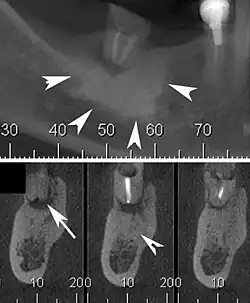

| Cone beam CT scan presenting a diffuse hyperdense lesion in the apex of a mandibular molar (arrowhead, top) adjacent to an inflammatory periapical lesion (arrow, bottom).[1] | |

Diagnosis typically involves a clinical examination by a dentist or endodontist, complemented by imaging studies such as cone-beam computed tomography. Radiographically, condensing osteitis presents as a localized radiopaque lesion at the root apex of the affected tooth.[5]